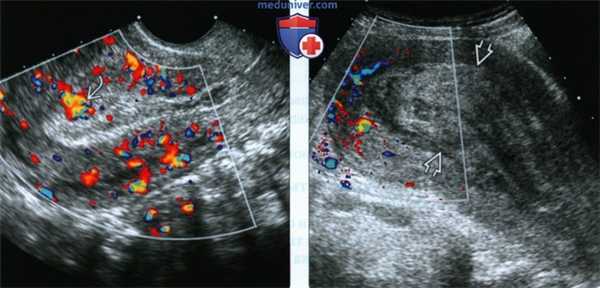

(Слева) ЗПЗ. Объемное образование в полости матки отсутствует, однако отмечается диффузное утолщение эндометрия с участком повышенного кровотока Повышенная васкуляризация утолщенного эндометрия в послеродовом периоде с высокой долей вероятности свидетельствует о ЗПЗ.

(Справа) В данном клиническом случае отмечается значительное утолщение эндометрия, однако при ЦДК кровоток отсутствует. Следует помнить, что в 40% случаев ЗПЗ кровоток при ЦДК минимален или отсутствует вовсе.